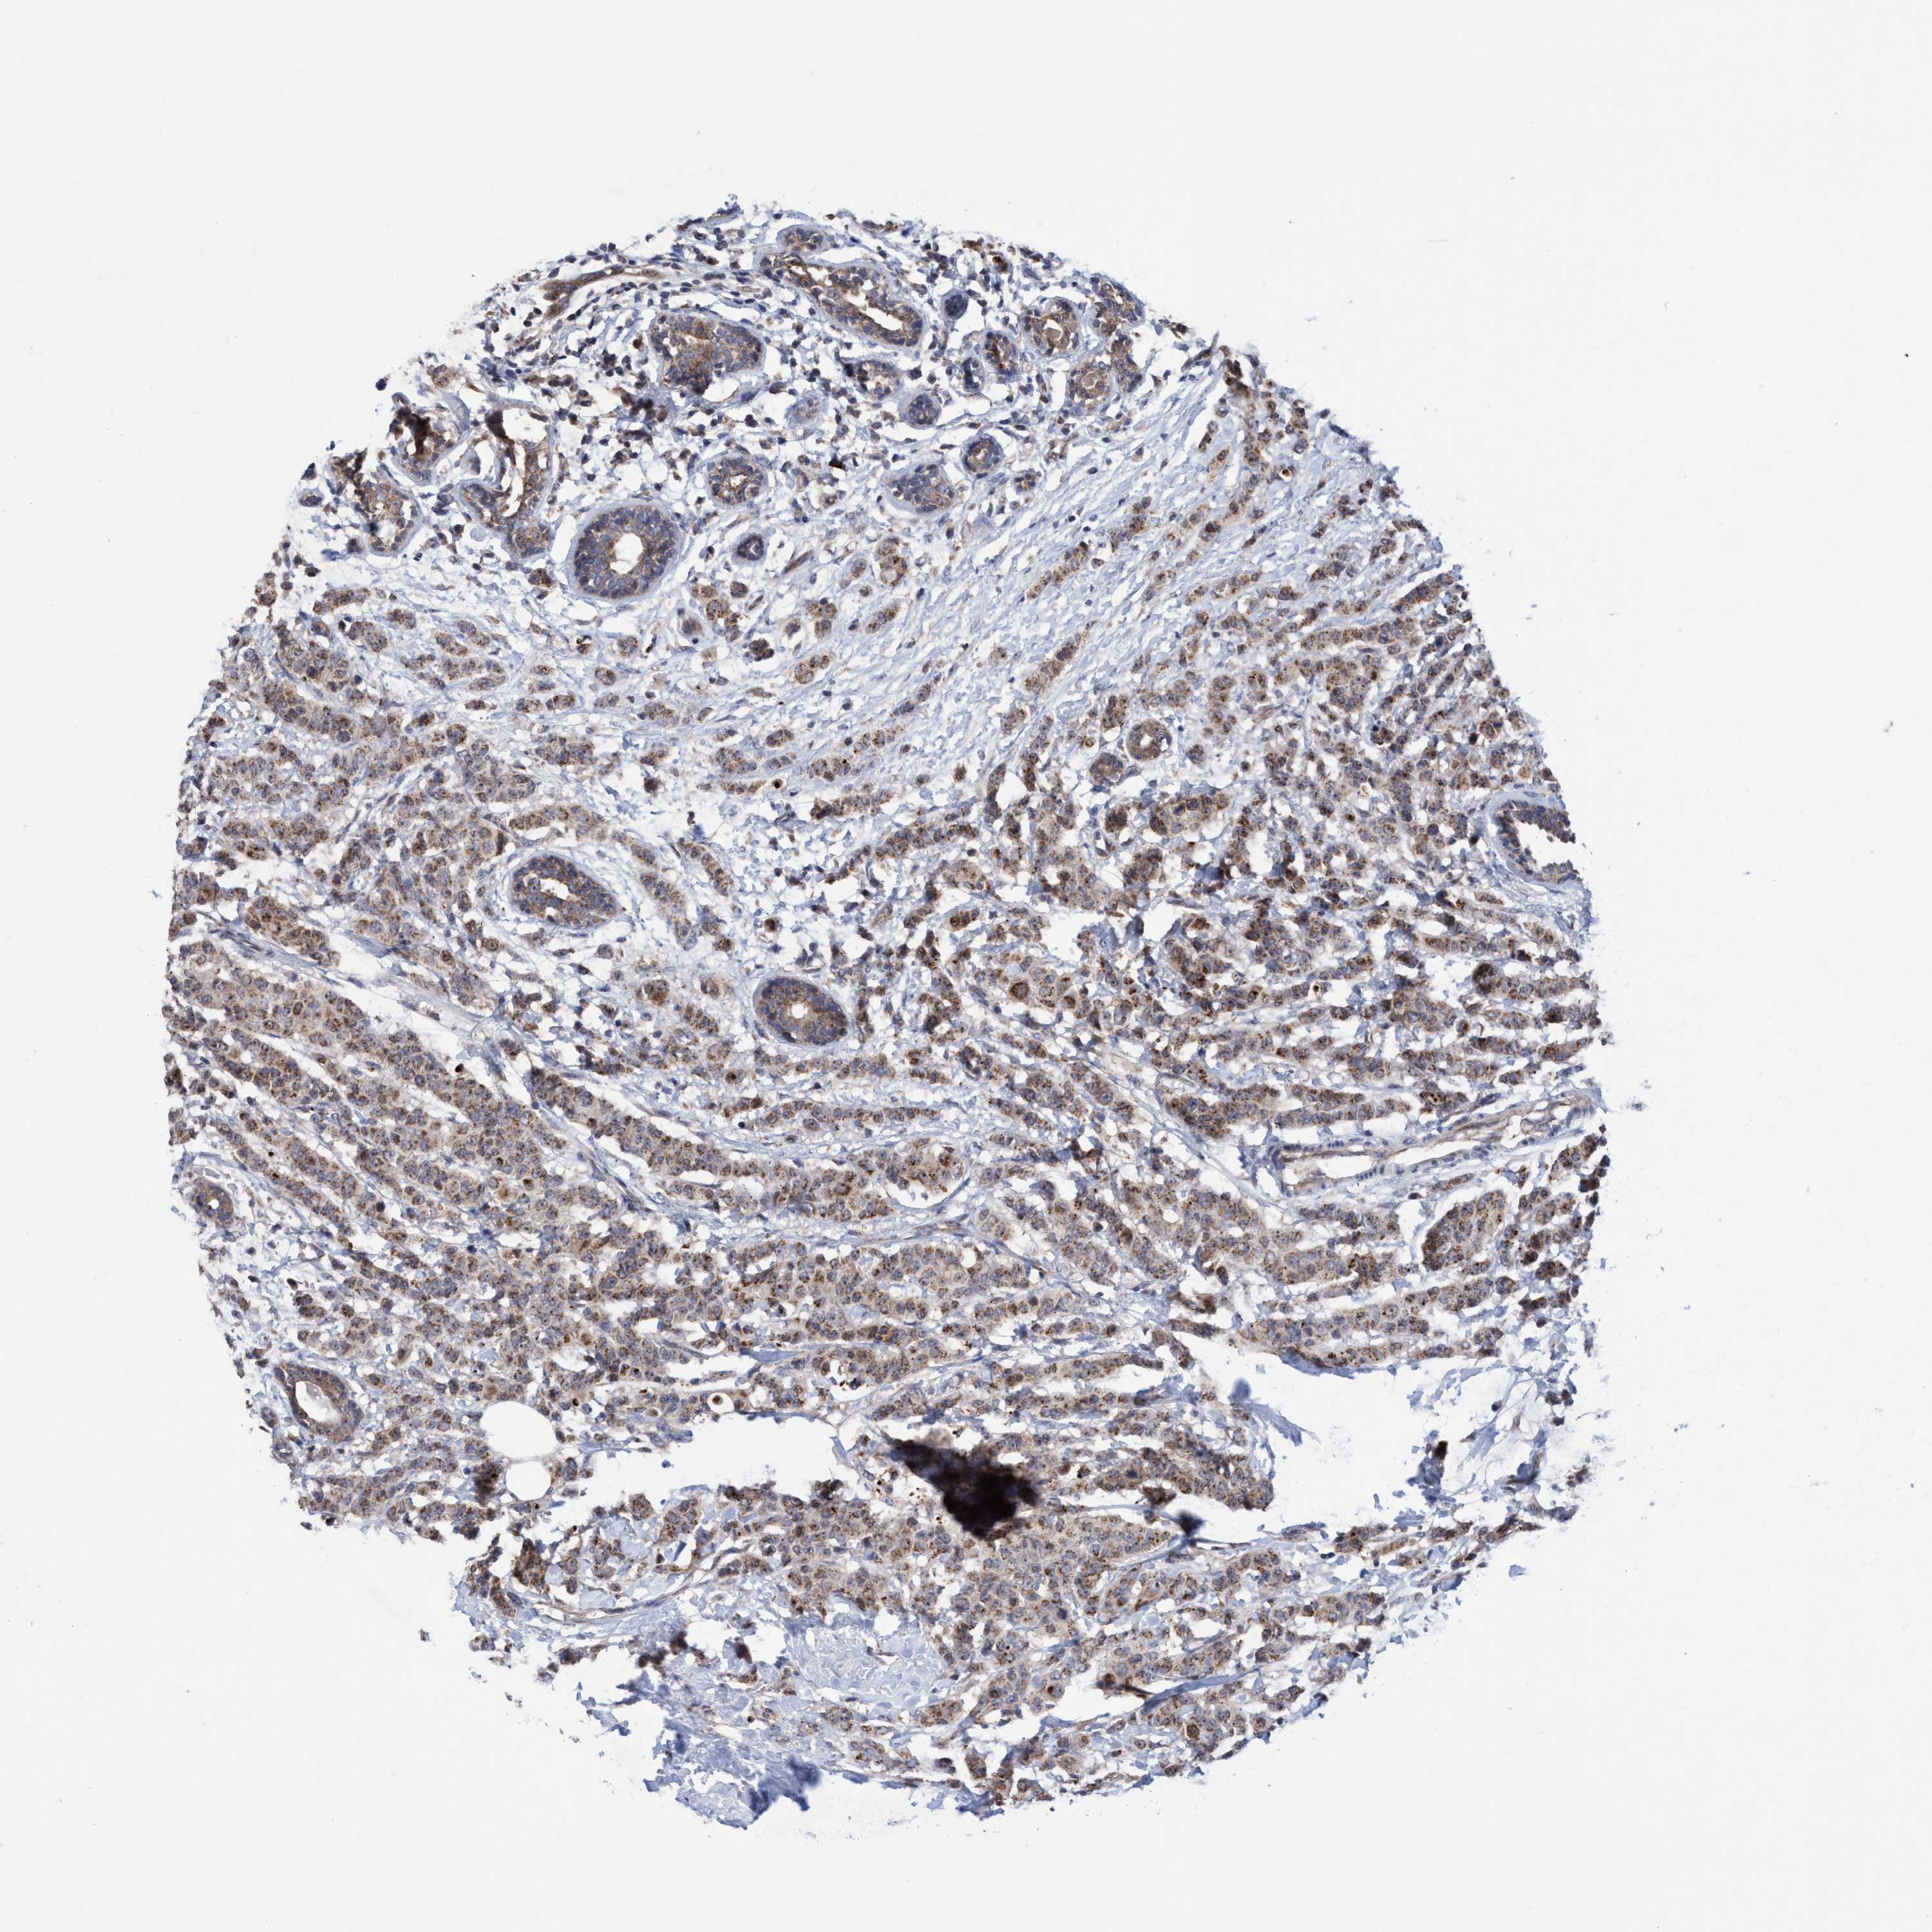

BRCA TCGA BRCA VALIDATION PROTEIN EXPRESSION

ANTIBODIES

AND

VALIDATION